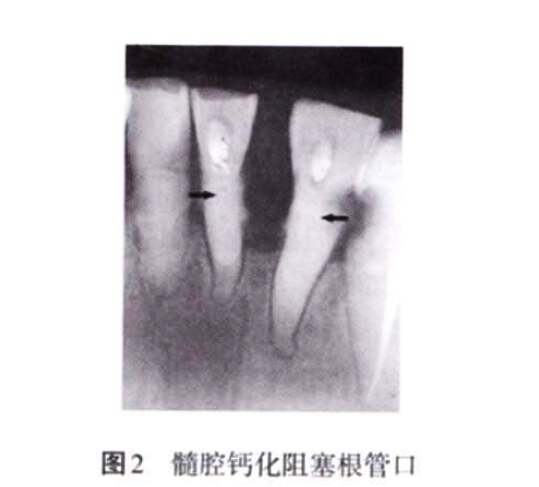

2. 2 未考慮髓腔的生理病理變化 髓腔的形態(tài)非一成不變,年齡的增長、外界物理和化學(xué)刺激、齲損等都會引起髓腔形態(tài)的改變,如髓腔體積變小、髓室頂和底的距離減小、髓腔鈣化阻塞根管口等,都會增加開髓難度(圖2)。術(shù)前如檢查不充分,未考慮髓腔的生理病理變化,并采取相應(yīng)的治療措施,常會導(dǎo)致在尋找根管口的過程中破壞髓室底,甚至出現(xiàn)穿孔。

3. 2. 2 髓腔鈣化 生理性或病理性刺激都會引起髓腔部分或全部鈣化,部分鈣化主要表現(xiàn)為髓石形成(圖7)。